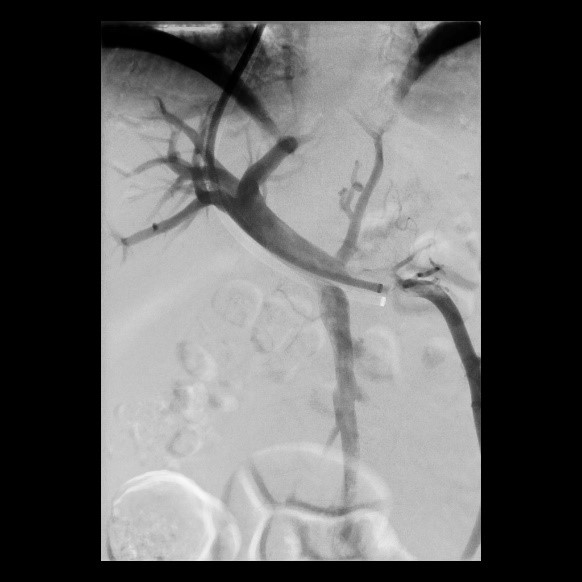

Postoperative abdominelle Blutungen bei chronischer Pankreatitis nach Embolisation der Art. gastroduodenalis mittels Metallspiralen (Coils)

(Bild 3 von 5)